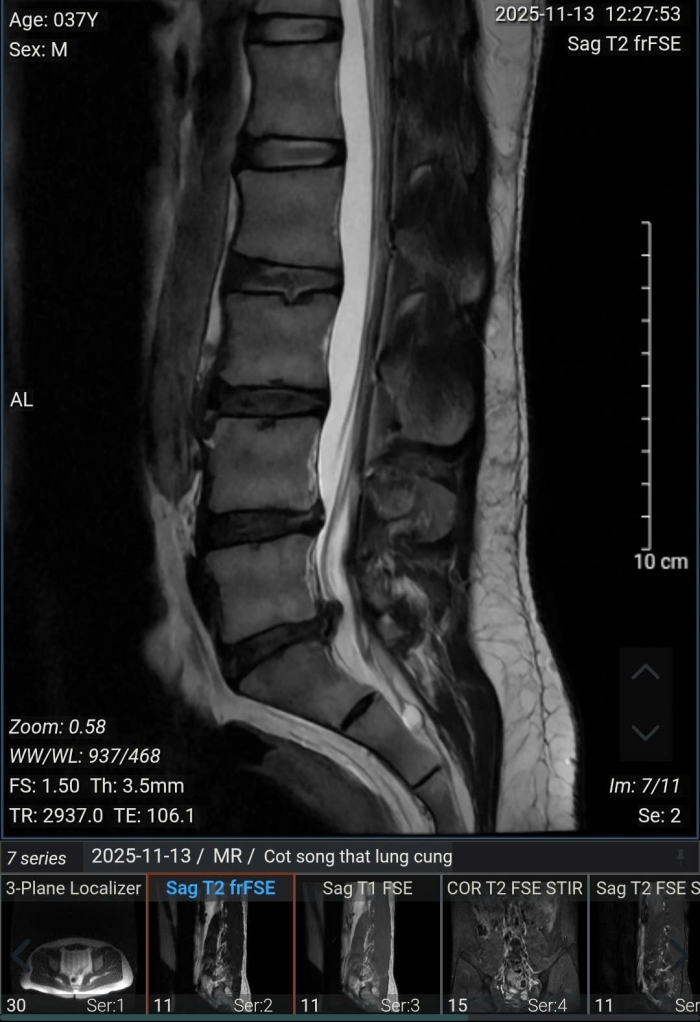

Kết quả chụp MRI cho thấy, bệnh nhân bị thoái hóa cột sống thắt lưng, thoát vị nội xốp các đĩa đệm từ L2/3 đến L5/S1, phình - thoát vị đĩa đệm L4/5 ra sau thể trung tâm gây chèn ép bao màng cứng, gây hẹp nhẹ ống sống, không gây chèn ép rõ rệt các rễ thần kinh; phình - thoát vị đĩa đệm L5/S1 ra sau thể trung tâm lệch trái gây chèn ép bao màng cứng, gây hẹp ống sống, hẹp ngách bên - lỗ tiếp và chèn ép các rễ thần kinh 1 bên ngang mức (trái > phải).

Ảnh chụp MRI của bệnh nhân nam 37 tuổi tại Hà Nội.